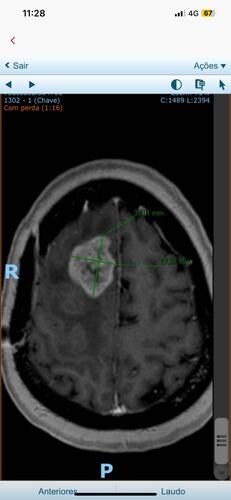

No dia 9 de outubro, uma nova ressonância com perfusão revelou um novo tumor de aproximadamente 4 cm, que já está causando inchaço e edemas em seu cérebro.